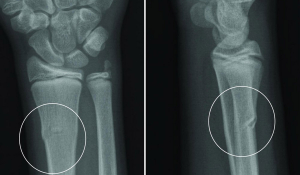

Перелом променевої кістки в «типовому місці»

Перелом саме променевої кістки є найпоширенішим травматичним пошкодженням передпліччя.

У 90% випадків причиною перелому є падіння на витягнуту руку.